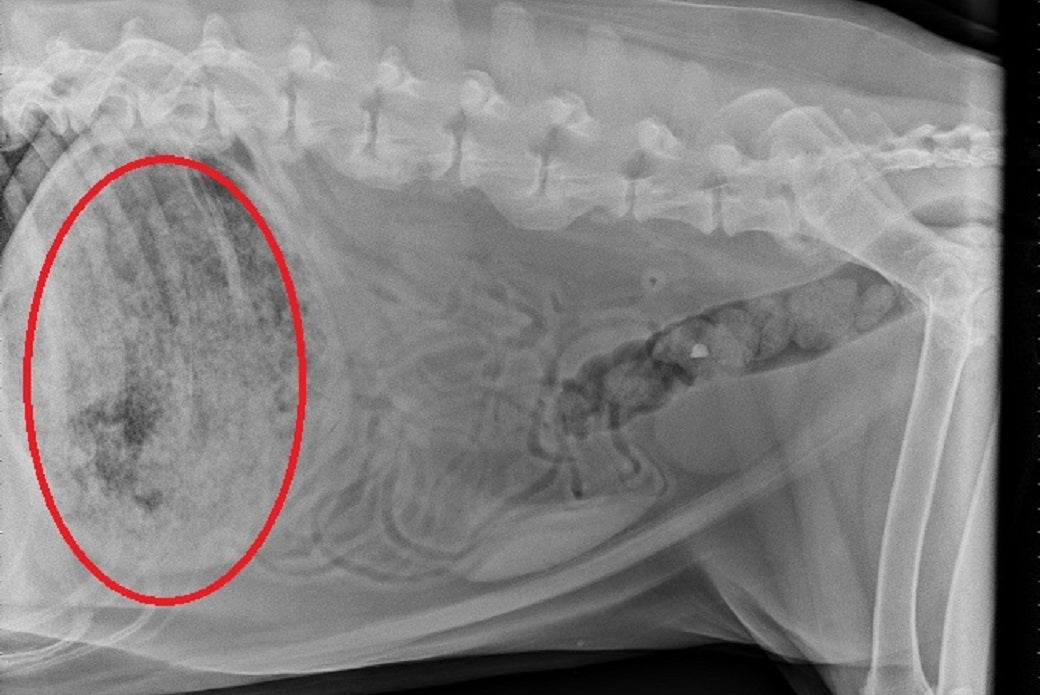

Frank, a computer repair specialist, and his mother, Erica, took She-Ra to their local Animal Specialty Center. X-rays showed a huge ball of hardened glue inside She-ra’s stomach. Veterinarians gave her a saline injection to prevent dehydration and advised against giving her food or water. The next morning at the ASPCA Animal Hospital (AAH) in Manhattan, She-ra underwent surgery.

X-rays showed hardened glue in She-ra’s stomach.

“After the glue hit her stomach, it expanded and filled it with a hard foam, making a hard cast from the inside,” explained Dr. Anna Whitehead, who performed She-ra’s surgery. “It stretches the stomach and can even kill the stomach wall depending on how much is ingested.”

(Left) X-ray showing the mass of hardened glue. (Right) Photo of She-ra courtesy of Frank Bauer.